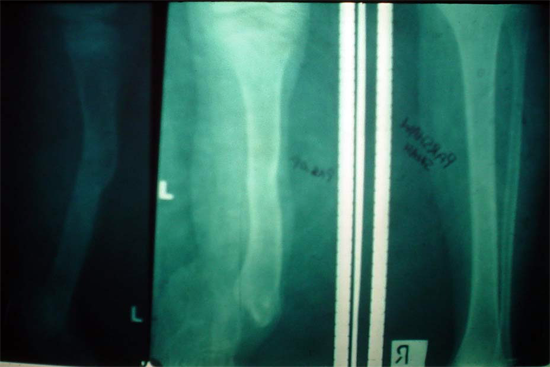

Limb Lengthening